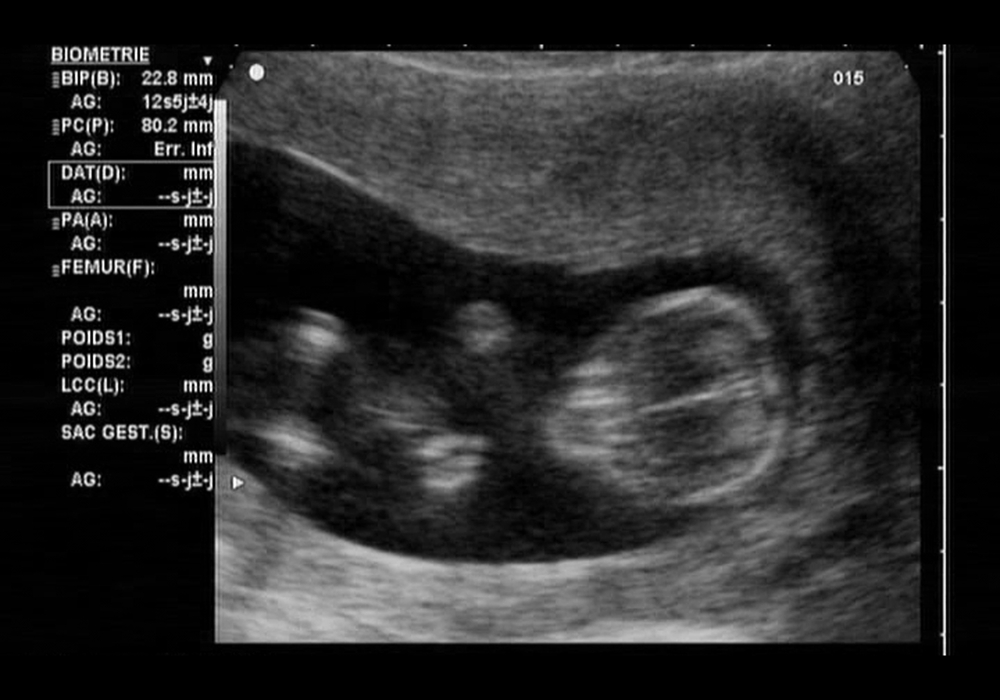

Pregnancy